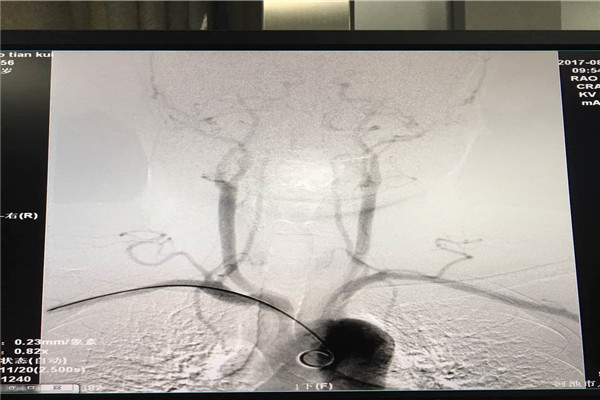

脑血管疾病因其发病率高、致残致死率高、复发率高等特点已经成为人民群众特别是老年人群的重要健康杀手。全脑血管造影是脑血管病诊断的金标准。传统全脑血管造影术(DSA术)主要经股动脉穿刺进行,虽然效果良好,但具有卧床时间长等缺点,为了让群众享受到更加方便快捷的诊疗服务,近日,我院神经内科二病区潘鹏克主任率领医疗团队凭借多年经股动脉穿刺途径行脑血管造影的经验,顺利完成经桡动脉入路进行全脑血管造影术,取得满意效果。

经桡动脉穿刺脑血管造影术是目前国内最先进的脑血管造影方式,与传统经股动脉穿刺脑血管造影相比,经桡动脉穿刺脑血管造影术具有手术创伤小、出血少、痛苦少、术后恢复快、安全性高、无需长时间卧床观察等优点,该项技术的开展将为河池脑血管疾病患者带来福音。